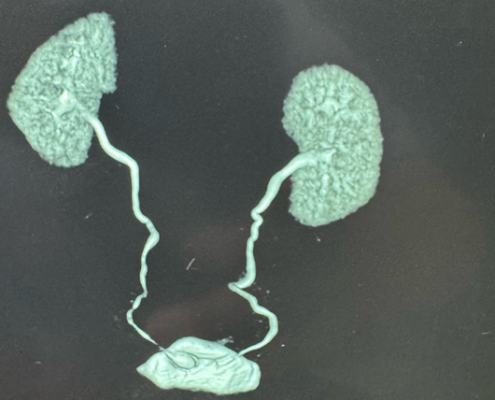

+ Bệnh nhân được chụp CT hệ niệu có tiêm thuốc cản quang kết quả: TD sỏi bàng quang vị trí lỗ niệu quản trái.

Hình 3 Hình ảnh Sỏi trên CT scanner hệ tiết niệu